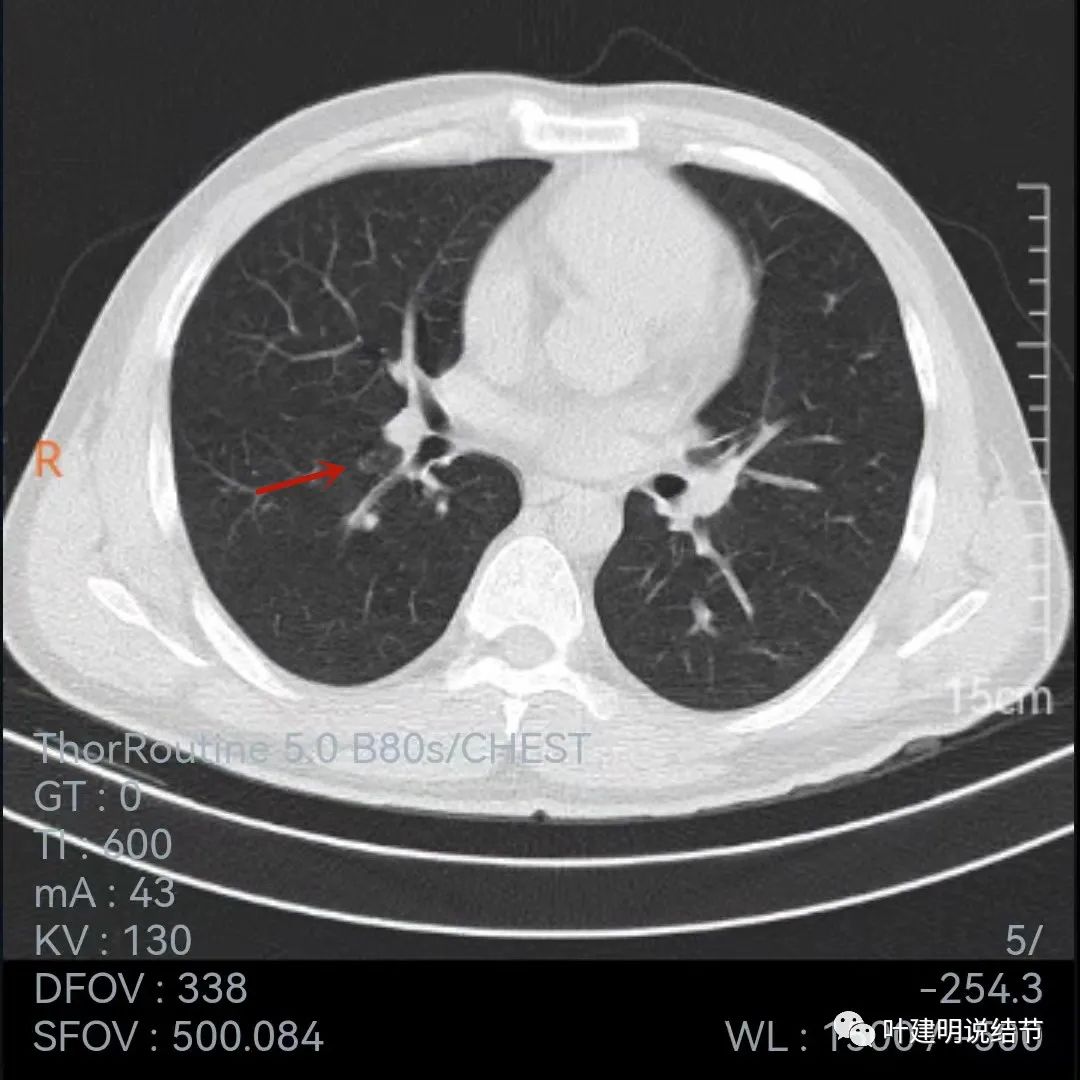

再看今年9月份的平扫片子:

也是三个层面可见,较去年也许略有增大,但测量起来可能差别不大,因为也是6-7毫米许。